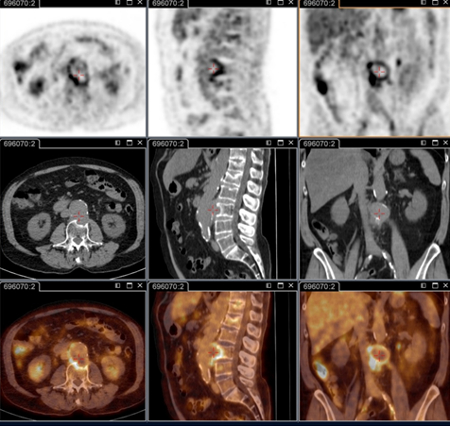

Q fever aortic mycotic lumbar aneurysm diagnosed at PET scan: 18F-fluorodeoxyglucose PET/CT. In this asymptomatic patient with heart valve history with elevated serology, the PET scan diagnosed an aortic endocarditis on native valve with thoracic and lumbar aortic mycotic aneurysms

Institut Hospitalo-Universitaire Méditerranée Infection (patient consent obtained)